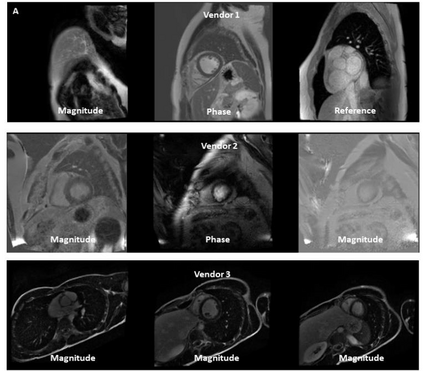

Objectives: To develop an image-based automatic deep learning method to classify cardiac MR images by sequence type and imaging plane for improved clinical post-processing efficiency. Methods: Multi-vendor cardiac MRI studies were retrospectively collected from 4 centres and 3 vendors. A two-head convolutional neural network ('CardiSort') was trained to classify 35 sequences by imaging sequence (n=17) and plane (n=10). Single vendor training (SVT) on single centre images (n=234 patients) and multi-vendor training (MVT) with multicentre images (n = 479 patients, 3 centres) was performed. Model accuracy was compared to manual ground truth labels by an expert radiologist on a hold-out test set for both SVT and MVT. External validation of MVT (MVTexternal) was performed on data from 3 previously unseen magnet systems from 2 vendors (n=80 patients). Results: High sequence and plane accuracies were observed for SVT (85.2% and 93.2% respectively), and MVT (96.5% and 98.1% respectively) on the hold-out test set. MVTexternal yielded sequence accuracy of 92.7% and plane accuracy of 93.0%. There was high accuracy for common sequences and conventional cardiac planes. Poor accuracy was observed for underrepresented classes and sequences where there was greater variability in acquisition parameters across centres, such as perfusion imaging. Conclusions: A deep learning network was developed on multivendor data to classify MRI studies into component sequences and planes, with external validation. With refinement, it has potential to improve workflow by enabling automated sequence selection, an important first step in completely automated post-processing pipelines.